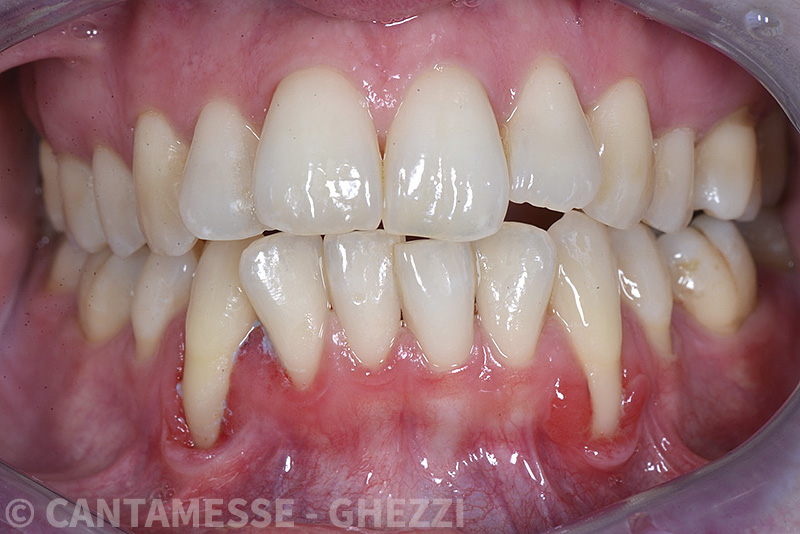

PREMESSA: in seguito all’estrazione dell’incisivo laterale superiore di destra, resasi necessaria per cause batteriche, si decide di affrontare il caso con il posizionamento di un impianto in sostituzione dell’elemento mancante dopo guarigione del sito infetto. Con tecniche rigenerative sia dei tessuti ossei mancanti a causa dell’infezione pregressa, sia dei tessuti gengivali che appaiono inizialmente troppo spostati in alto, si ripristina una corretta morfologia delle parabole (contorni) gengivali e delle papille interdentali (triangoli di gengiva tra due denti vicini).

Vengono utilizzati 2 tipi di provvisori: il primo, cementato ai denti vicini, viene utilizzato dal momento dell’estrazione del dente fino ad impianto osteointegrato (circa 6 mesi); il secondo, avvitato direttamente all’impianto, ha una funzione di prova estetica ma soprattutto di guida per la maturazione dei tessuti gengivali peri-implantari portandoli verso la maturazione completa prima di posizionare la corona finale in disilicato di litio.